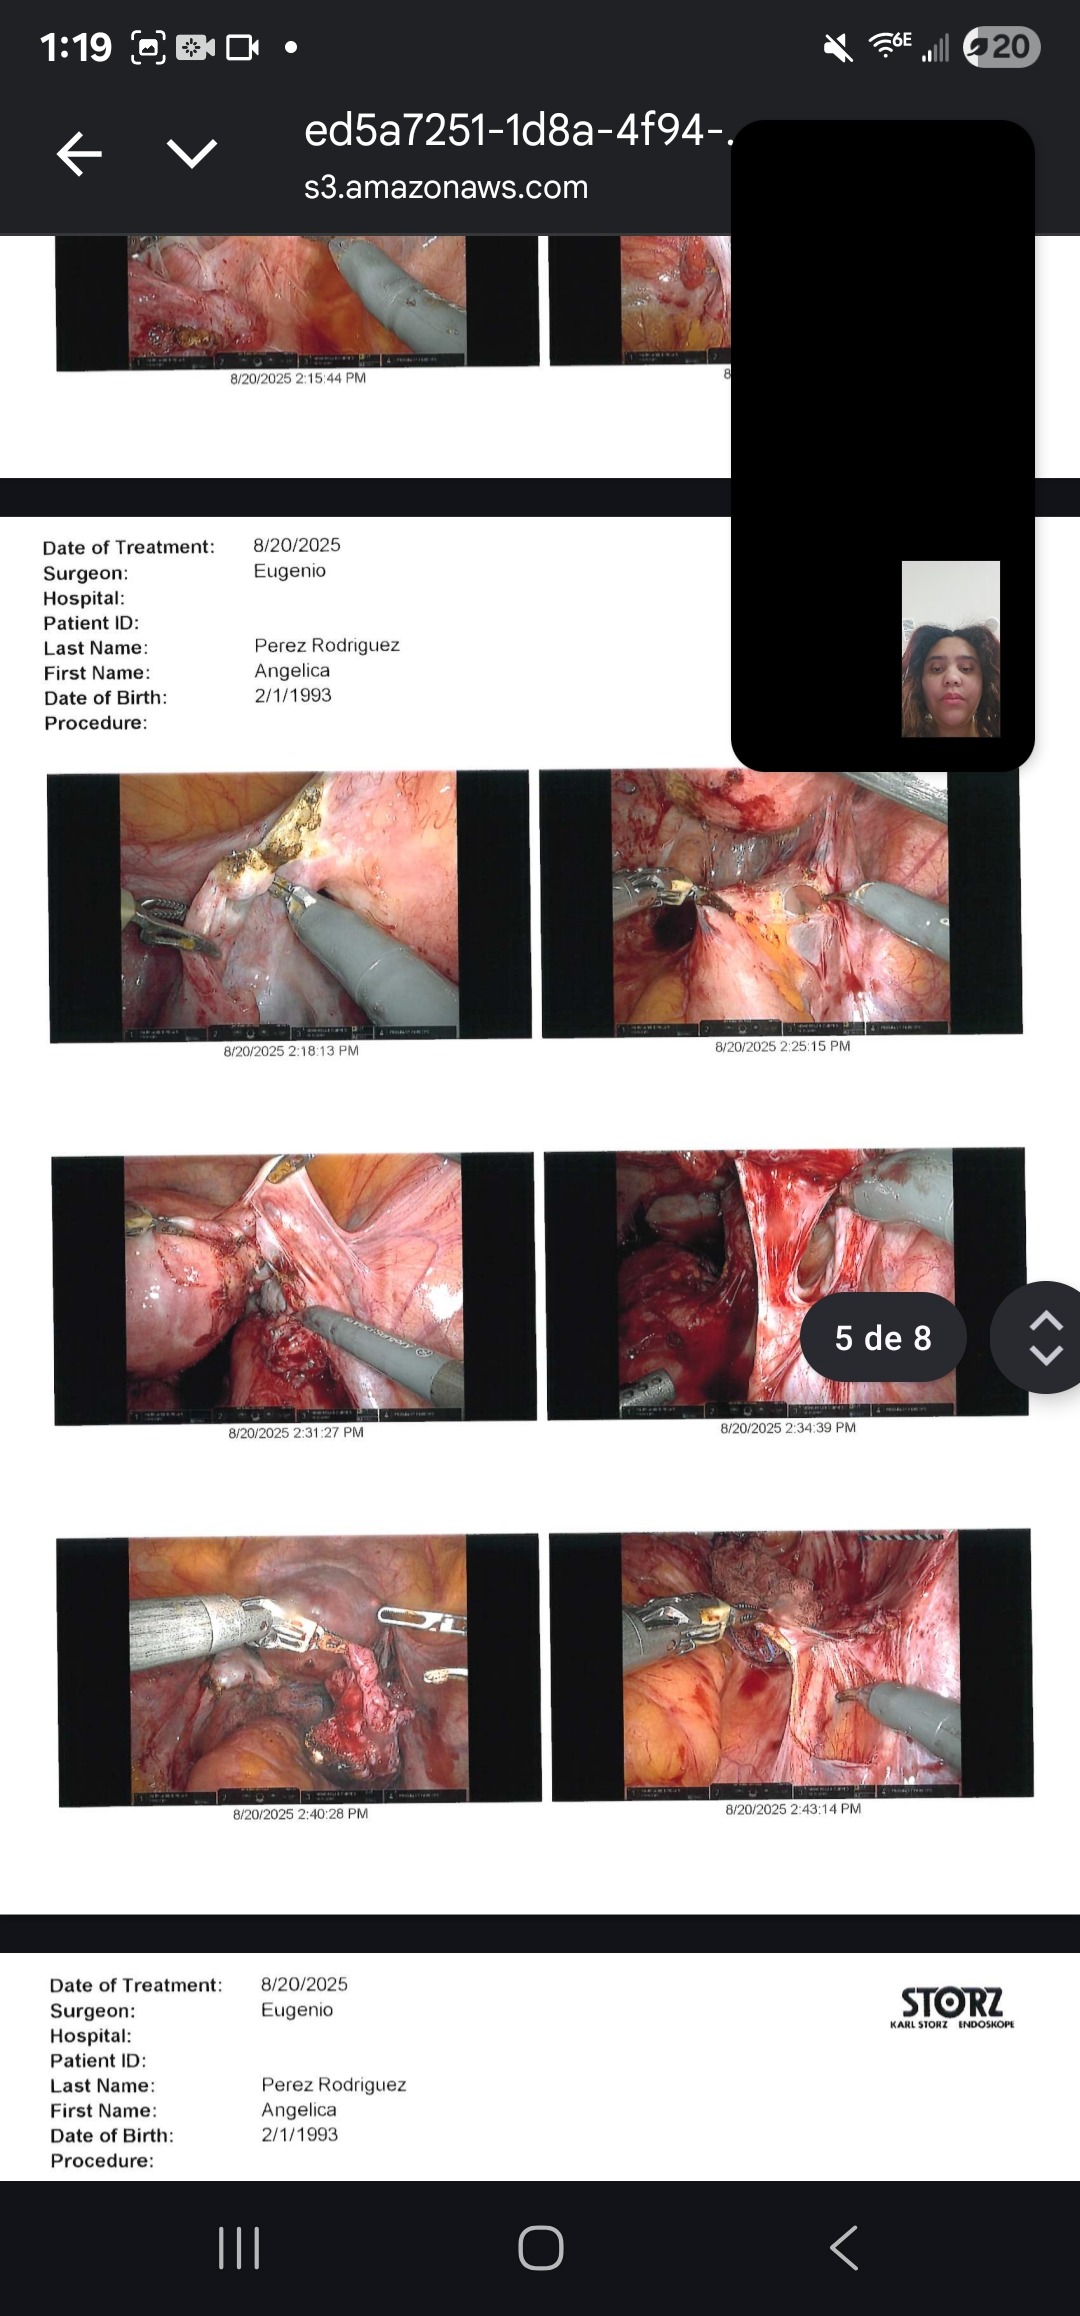

My name is Angelica, and I am fighting Stage 4 deep infiltrative endometriosis. Since 2022, I have gone through 5 surgeries — 3 of them just in the past year. Each operation has been an attempt to ease the pain and give me a chance at a normal life, but the fight is far from over.